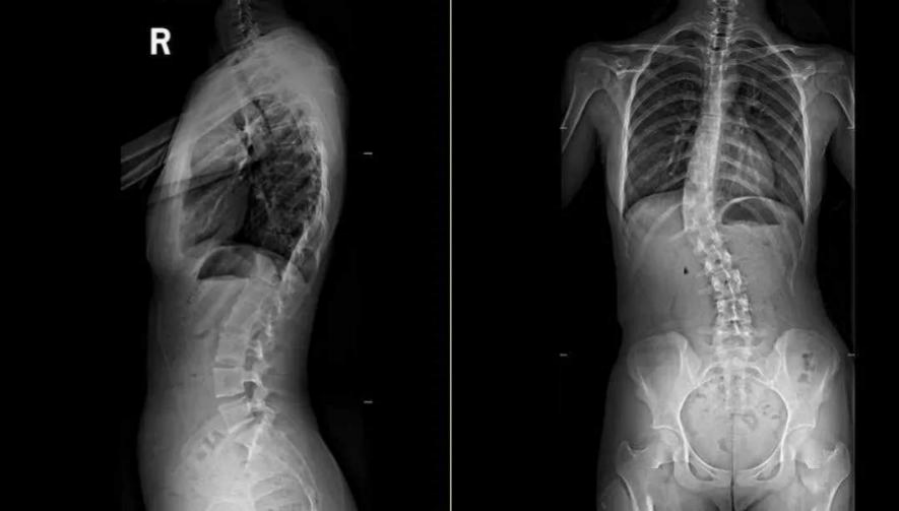

父母带其就诊,全脊柱X光显示:胸弯Cobb角45°、腰弯40°,双弯僵硬、椎体旋转明显,已达重度脊柱侧弯,保守治疗无效,必须手术。